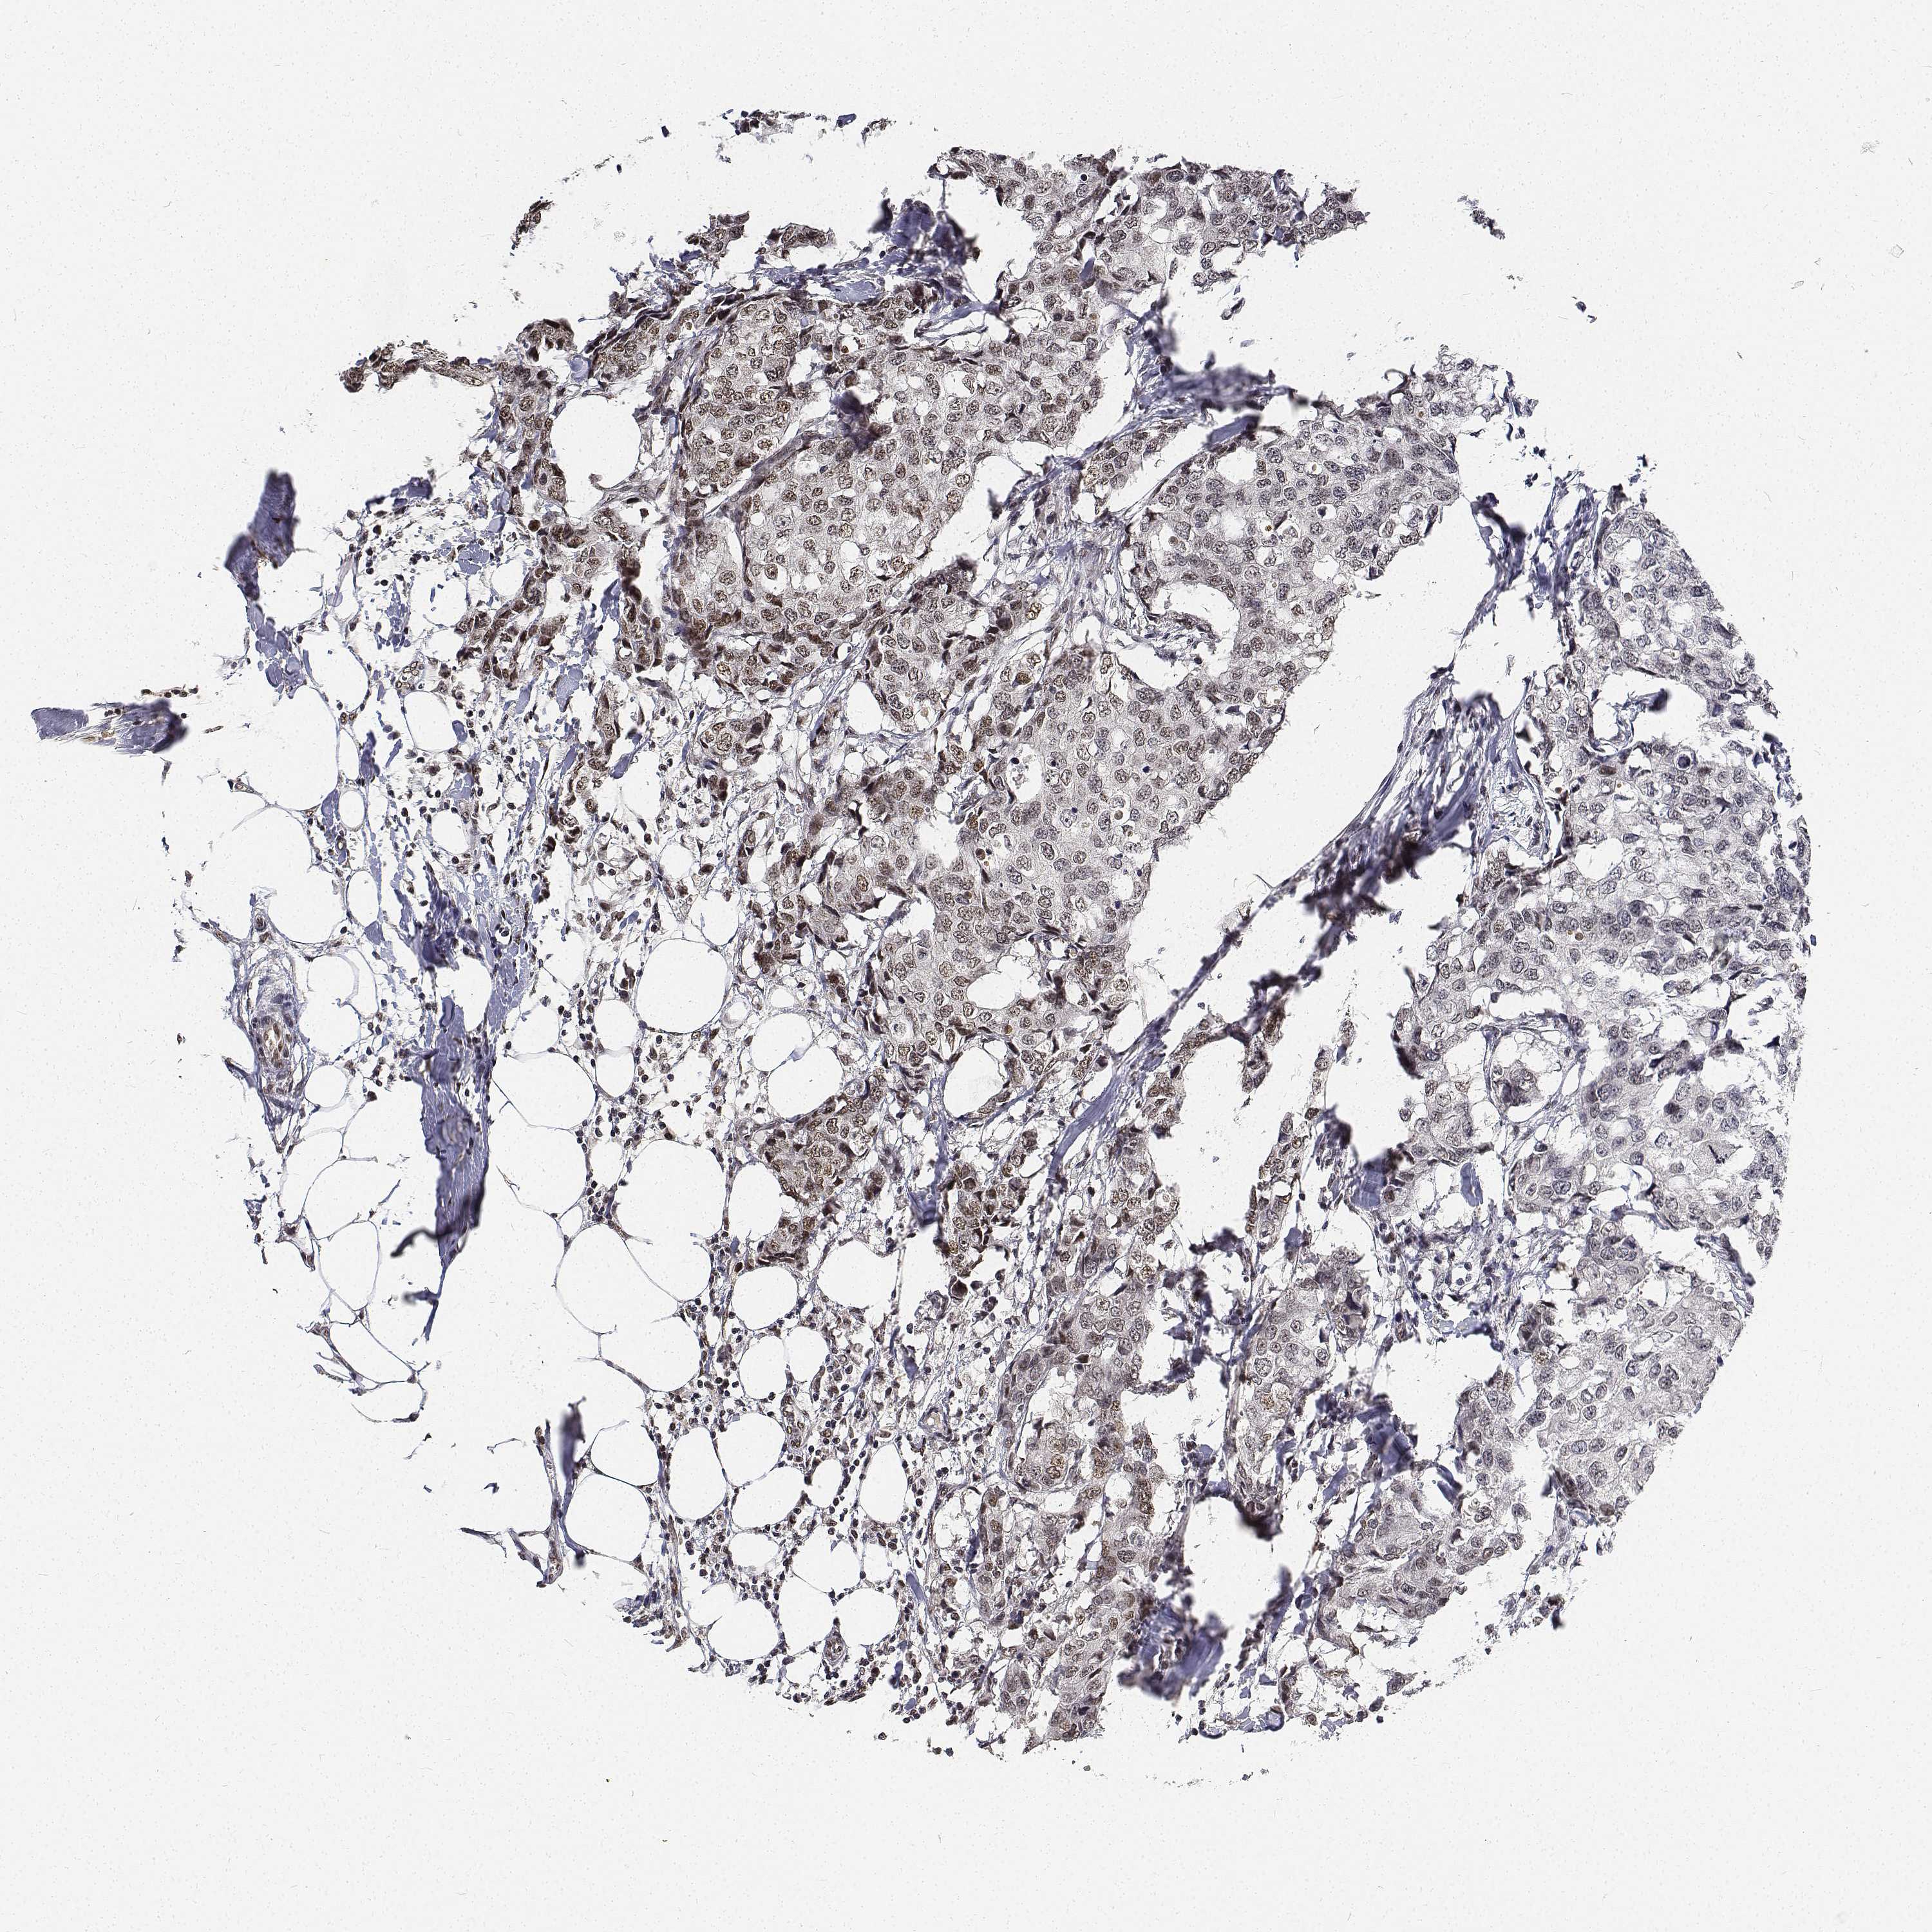

CANCER BREAST CANCER Show tissue menu

BRCA TCGA BRCA VALIDATION PROTEIN EXPRESSION